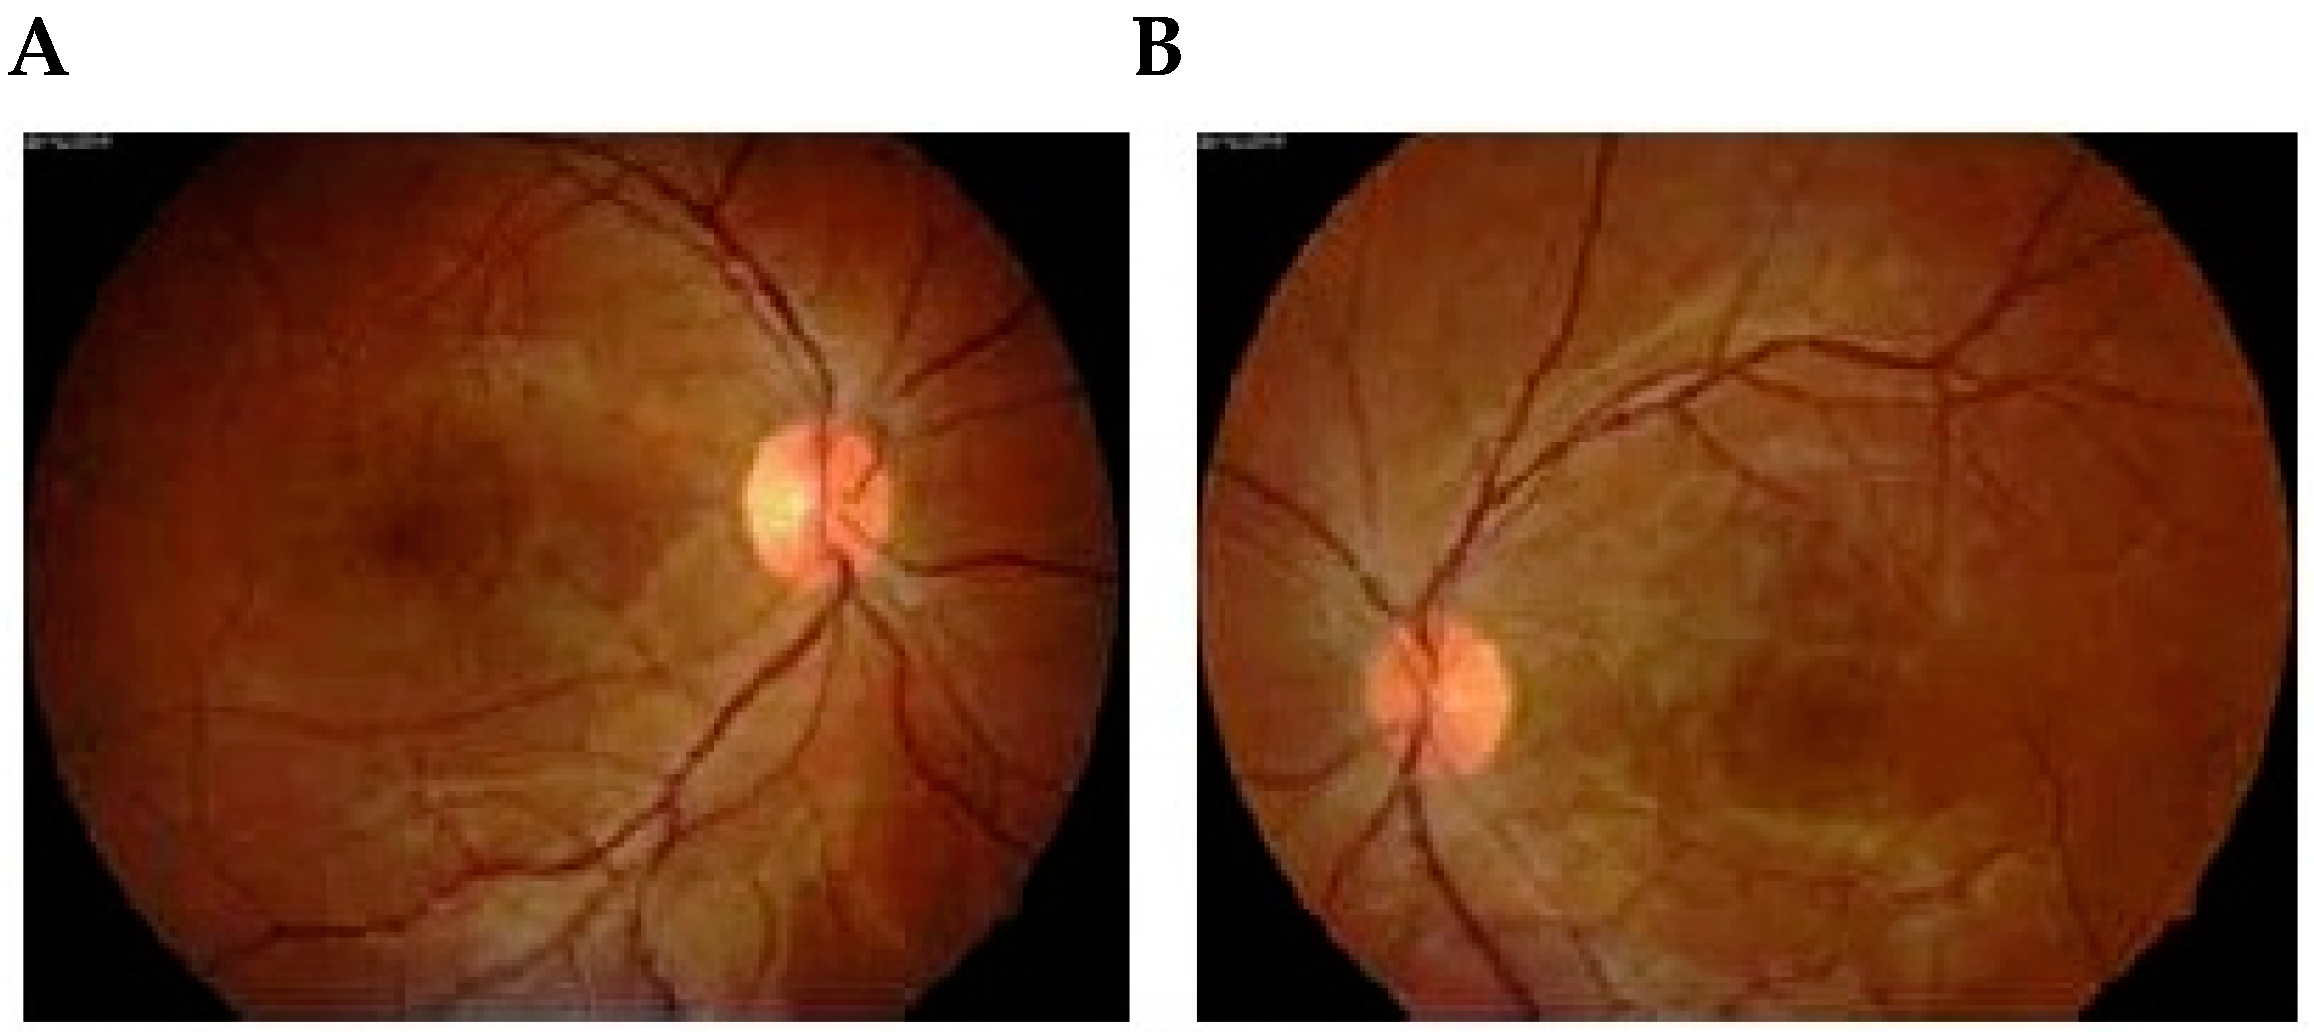

2. Fluorescein Angiography and Indocyanine Green Angiography in Hypertensive Diseases of Pregnancy

2.1. Fluorescein Angiography

- Kwok, A.H.; Li, J.; Lai, T.Y.; Chan, W.M.; Bhede, P.; Lam, D.S. Multifocal electroretinographic and angiographic changes in preeclampsia. Br. J. Ophthalmol. 2001, 85, 111–112. [Google Scholar] [CrossRef] [PubMed]